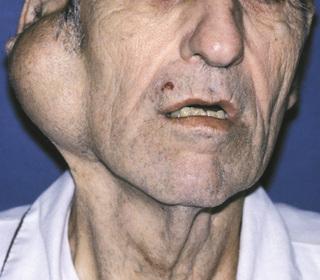

Enlargement of the parotid and submandibular glands secondary to alcoholism. Sialography demonstrates a “leafless tree” pattern.

sialadenosis